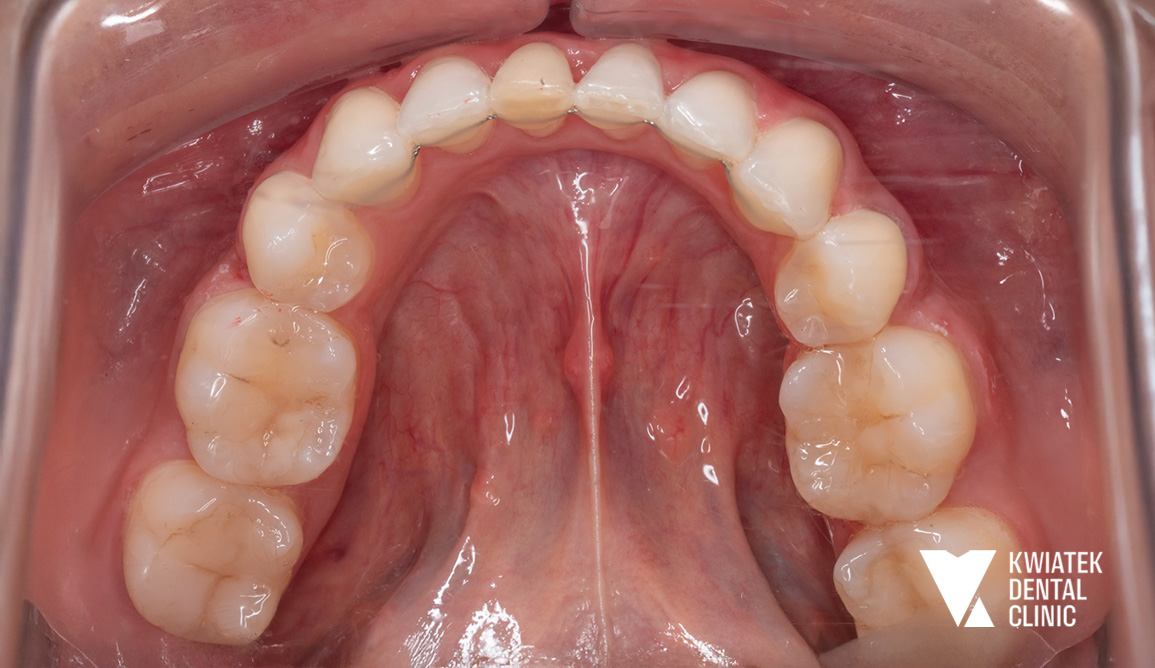

PO

Po zakończeniu leczenia aktywnego zastosowano retainery stałe oraz ruchome, aby utrwalić uzyskany efekt i zapewnić jego długoterminową stabilność.

Uzyskano:

• eliminację ognisk próchnicy i stanów zapalnych

• odbudowę funkcji zębów

• prawidłowe ustawienie zębów w łukach

• zamknięcie przestrzeni po ekstrakcjach

• poprawę relacji zgryzowych

• naturalny, harmonijny uśmiech